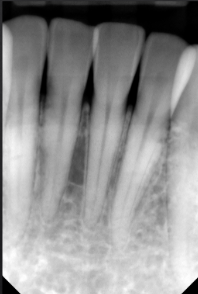

normal alveolar bone

first sign of bone loss is loss of cortication of interproximal bone

alveolar crest health